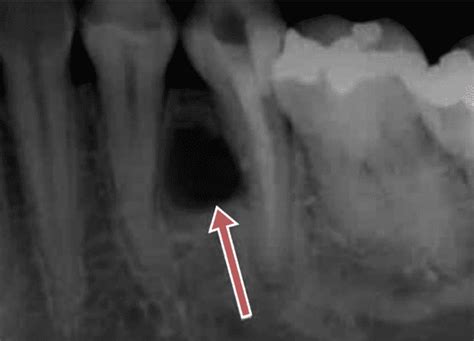

Diagnóstico de Quistes Maxilares

Para poder diferenciar un quiste de otro tipo de lesiones, el dentista debe tener en cuenta los síntomas que presenta el paciente, así como la ubicación del quiste. Una adecuada exploración clínica y radiográfica por parte del odontólogo es suficiente para alcanzar un diagnóstico de presunción. Para saber a qué categoría pertenece un quiste maxilar es fundamental realizar una exploración clínica y radiográfica.

El principal método para detectar un quiste maxilar es a través de una radiografía, en la que se puede observar una mancha de color oscuro en el hueso. Una vez que el dentista sepa de la presencia del quiste, es posible que solicite pruebas adicionales, tales como una tomografía computarizada o una biopsia, que le permitan tener una información más completa y detallada sobre el tipo de quiste, la extensión del mismo y sus características. Aspectos como el tamaño del quiste, las estructuras anatómicas vecinas o la evolución de su aspecto o color, ayudan a identificar el tipo de quiste y a aplicarle el tratamiento correcto.